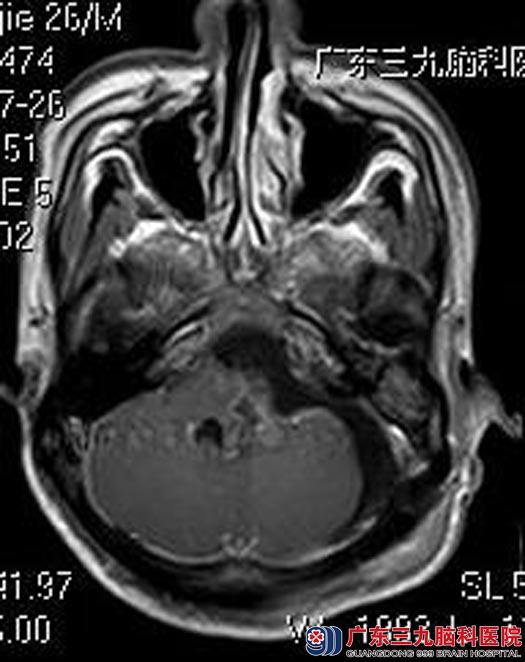

鲁明主任主刀,在全麻下经左侧乙状窦后入路行左侧桥小脑角区多发肿瘤切除术,脑压板轻抬小脑,见多发肿瘤,其中一个大小约1.0cm×0.8cm×1.0cm,起源于副神经,黄白色,血供一般,与后组颅神经粘连紧密,质软,显微镜下予以钝性分离;另一肿瘤起源于内听道,左侧面听神经粘连紧密,予显微镜下分块切除,术中全程电生理监测,术毕面听神经电刺激反应良好。术后无后组颅神经损害症状,耳鸣症状明显好转。术后病理结果提示:神经鞘膜瘤。